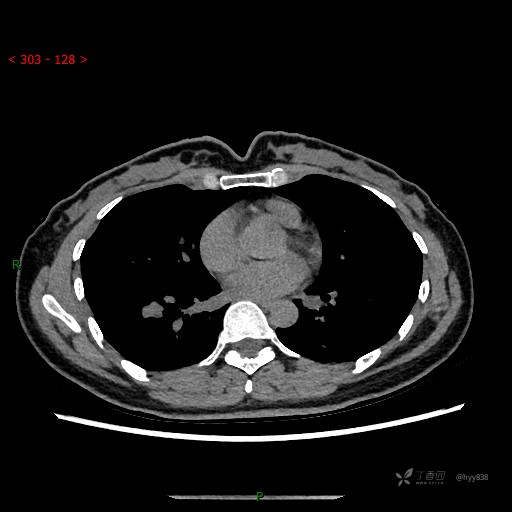

增强动脉期